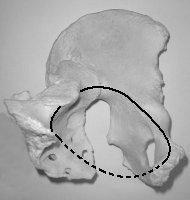

C'est un os plat, pair et non symétrique, vrillé en forme d'hélice (fig. b). Il forme avec son homologue et le sacrum la ceinture pelvienne qui unit le membre inférieur au tronc.

Il s'articule en DH avec le fémur ;

en DD et en AV avec son homologue ; en DD et en ARR avec le sacrum.

L'os coxal possède un trou, 4 bords (supérieur / antérieur / postérieur

/ inférieur) et 2 faces (médiale ou

endopelvienne / latérale ou

exopelvienne).

| fig.

a Vue externe os coxal G

Il est constitué embryologiquement de trois parties soudées (fig. a) :

articulaire avec le fémur : acetabulum (old. cavité cotyloïde ou cotyle). |

La crête iliaque est au niveau de la 4ième lombaire (L4). Cet os présente des variations sexuelles notamment un diamètre interne plus large chez la femme Détroit supérieur (concept obstétricale)  |

fig. b Vue antérieure os coxal G |

On distingue 3 segments (fig. b) : - supérieur : c'est l'aile iliaque, aplatie et large (elle regarde en DH et en ARR),- moyen : région de l'acétabulum (porte la cavité articulaire avec le fémur). - inférieur (c'est le pourtour osseux du foramen ischio-pubien (il déborde en AV et en DD) |

L'épine

iliaque

antéro-supérieure (2), l'épine iliaque postéro-supérieure, la crête

iliaque (3), la tubérosité ischiatique (en position assis), la symphyse

pubienne.

Obstétrie

: la ligne arquée forme le détroit supérieur (passage premier lors de

l'accouchement). Diamètre transverse médian = 12,5 à 13 cm, diam.

antéro-post = 10,5 cm.